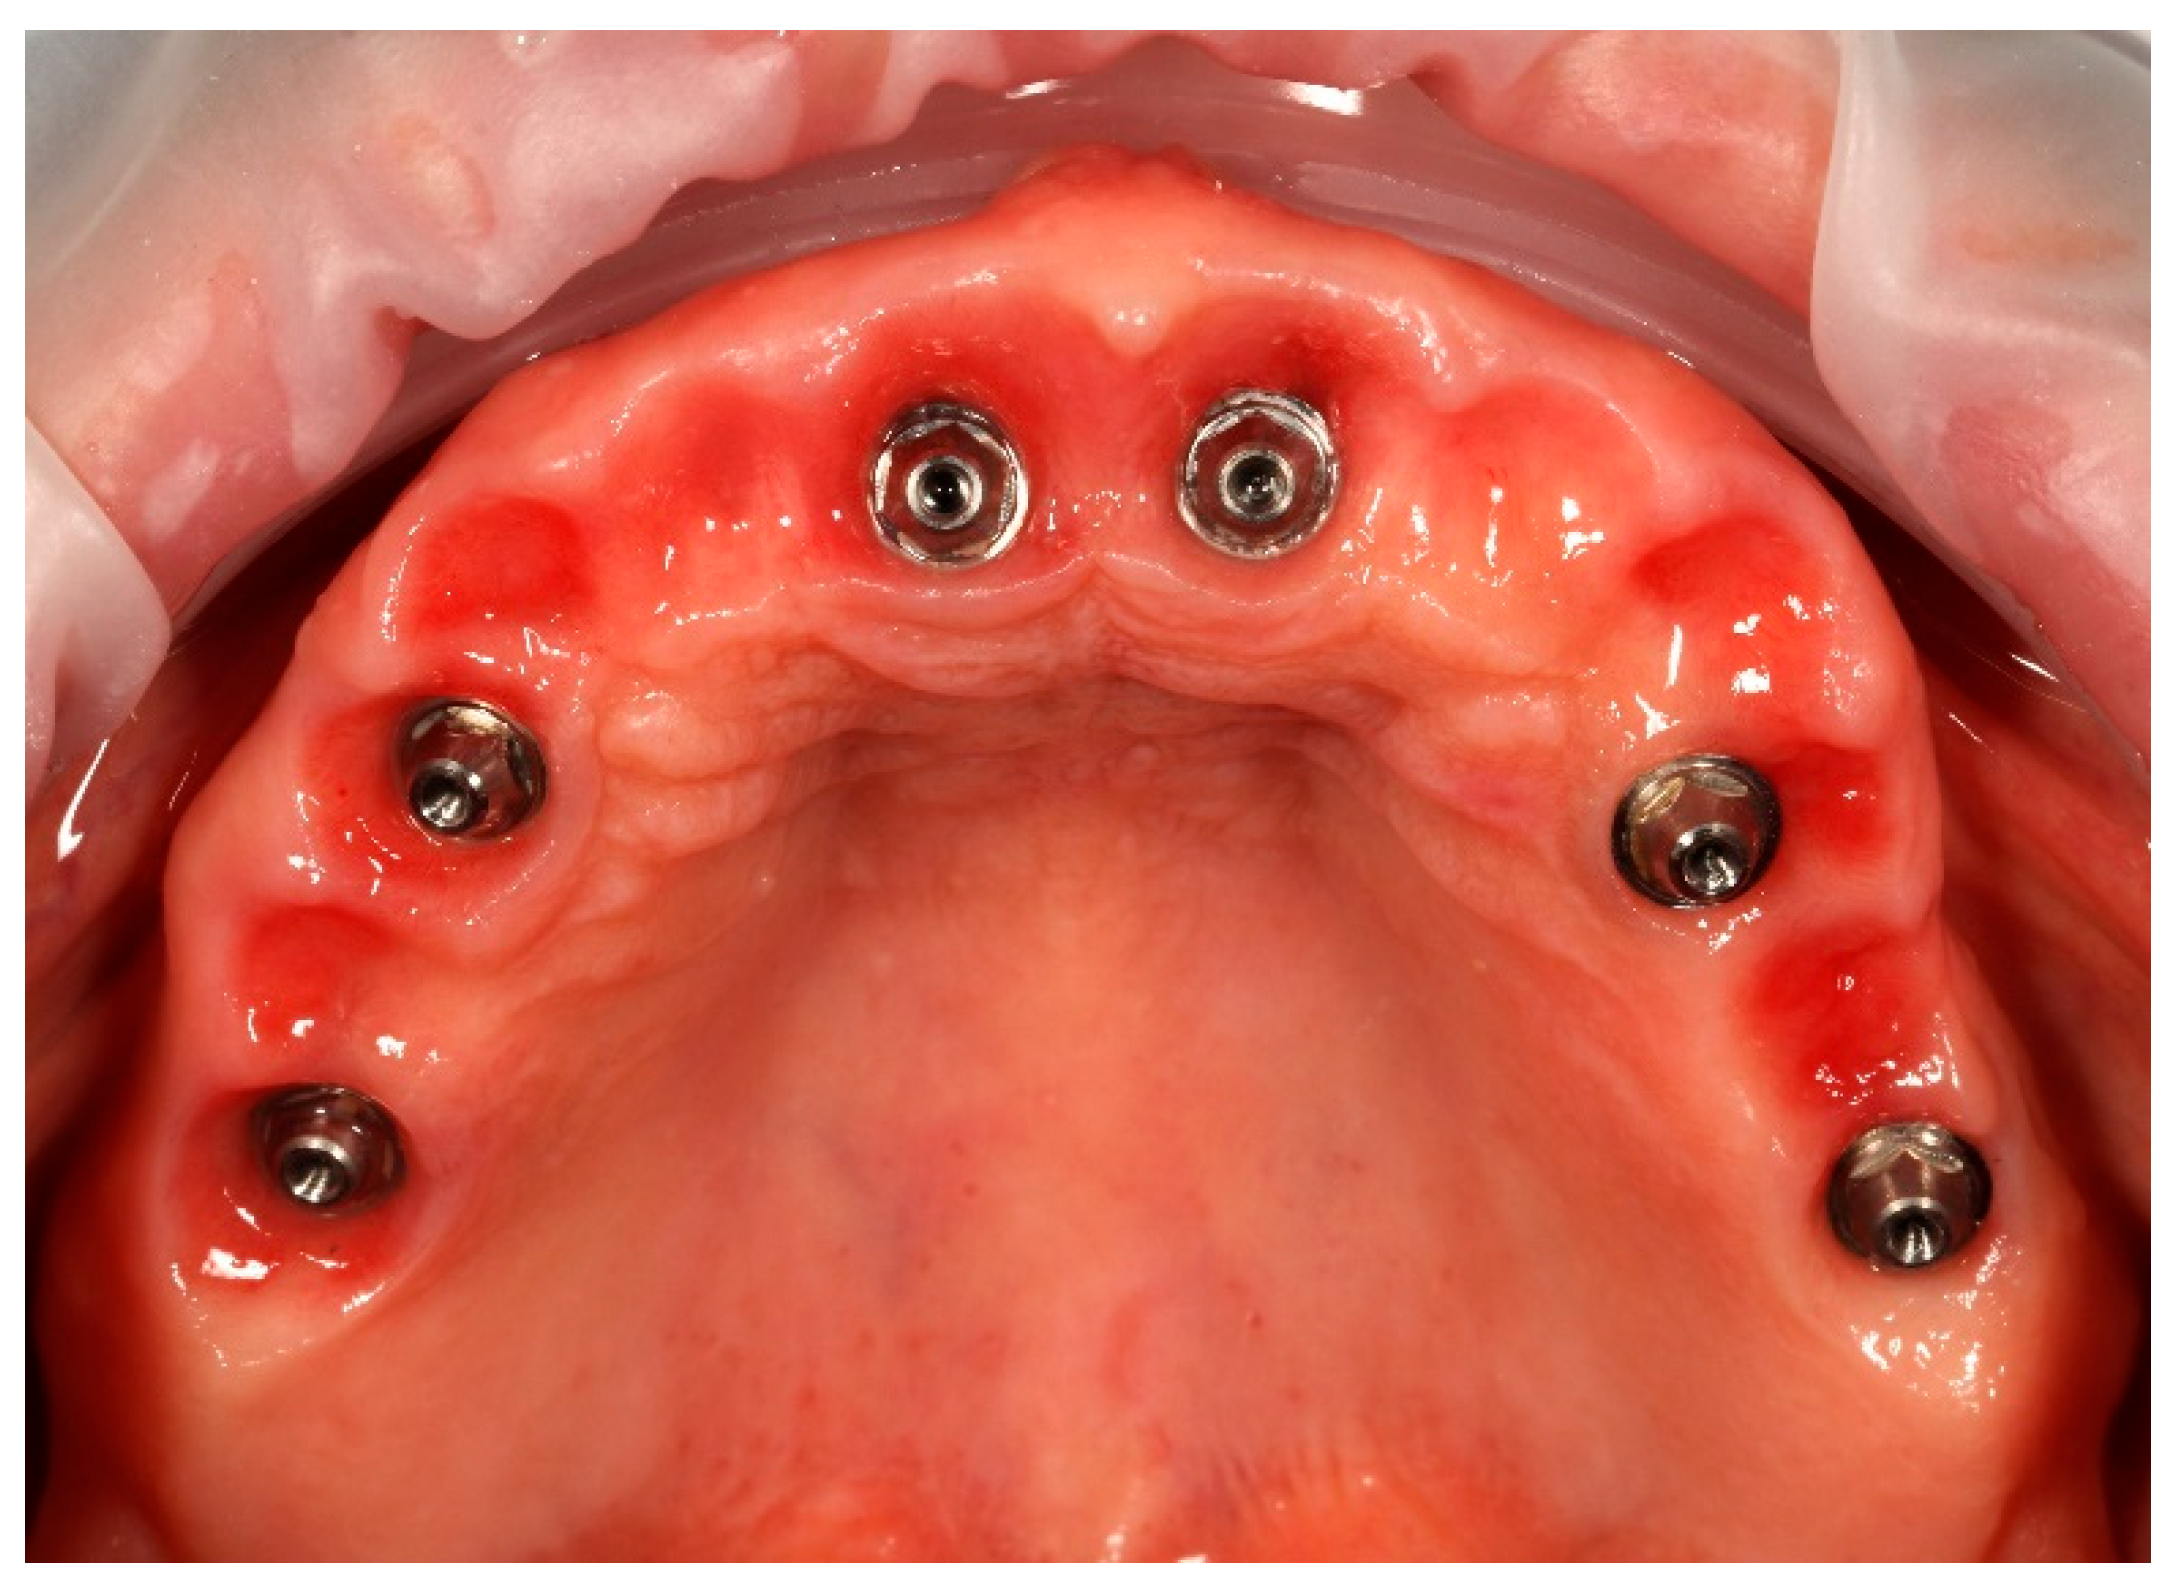

Simultaneously, the existing implant-supported crowns in positions 16 and 26, as well as the anterior implant-supported bridge, were unscrewed from the supporting implants. Multi-unit abutments were then selected and secured onto all six supporting implants, including the newly placed implants at sites 14 and 24 (Figure 4).

Figure 4. Multi-unit abutments secured onto all six supporting implants, including the newly placed implants at positions 14 and 24, following removal of the existing restorations.